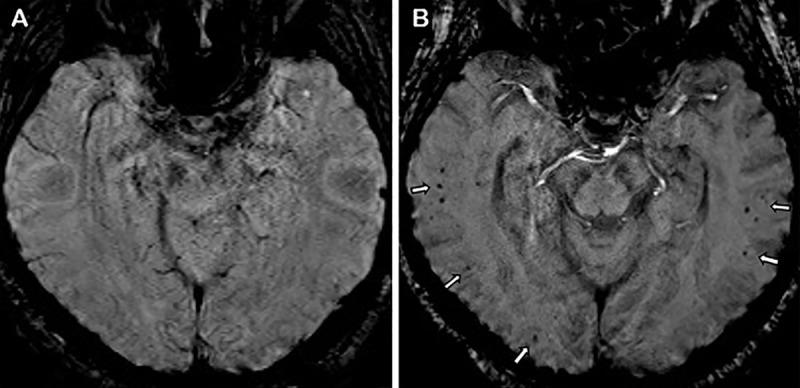

Diffuse leukoencephalopathy and juxtacortical and/or callosal microhemorrhages were brain imaging features in critically ill patients with coronavirus disease 2019. Coronavirus disease 2019 (COVID-19) has been reported in association with a variety of brain imaging findings such as ischemic infarct, hemorrhage, and acute hemorrhagic necrotizing encephalopathy. Herein, the authors report brain imaging features in 11 critically ill patients with COVID-19 with persistently diminished mental status who underwent MRI between April 5 and April 25, 2020. These imaging features include confluent T2 hyperintensity and mild restricted diffusion in bilateral supratentorial deep and subcortical white matter (in 10 of 11 patients) and multiple punctate microhemorrhages in juxtacortical and callosal white matter (in seven of 11 patients). The authors also discuss potential pathogeneses.

弥漫性脑白质病和皮质下及/或胼胝体微出血是 COVID-19 危重症患者的脑部影像学特征。有报道称,COVID-19(新冠肺炎)与多种脑部影像学表现相关,如缺血性梗死、出血和急性出血性坏死性脑病。在此,作者报告了 11 例 COVID-19 危重症患者的脑部影像学特征,这些患者的精神状态持续减退,于 2020 年 4 月 5 日至 4 月 25 日期间接受 MRI 检查。这些影像学特征包括 11 例患者中有 10 例双侧大脑半球深部和皮质下白质存在融合性 T2 高信号和轻度弥散受限,以及 7 例患者存在皮质下和胼胝体白质内多发性点状微出血。作者还讨论了潜在的发病机制。